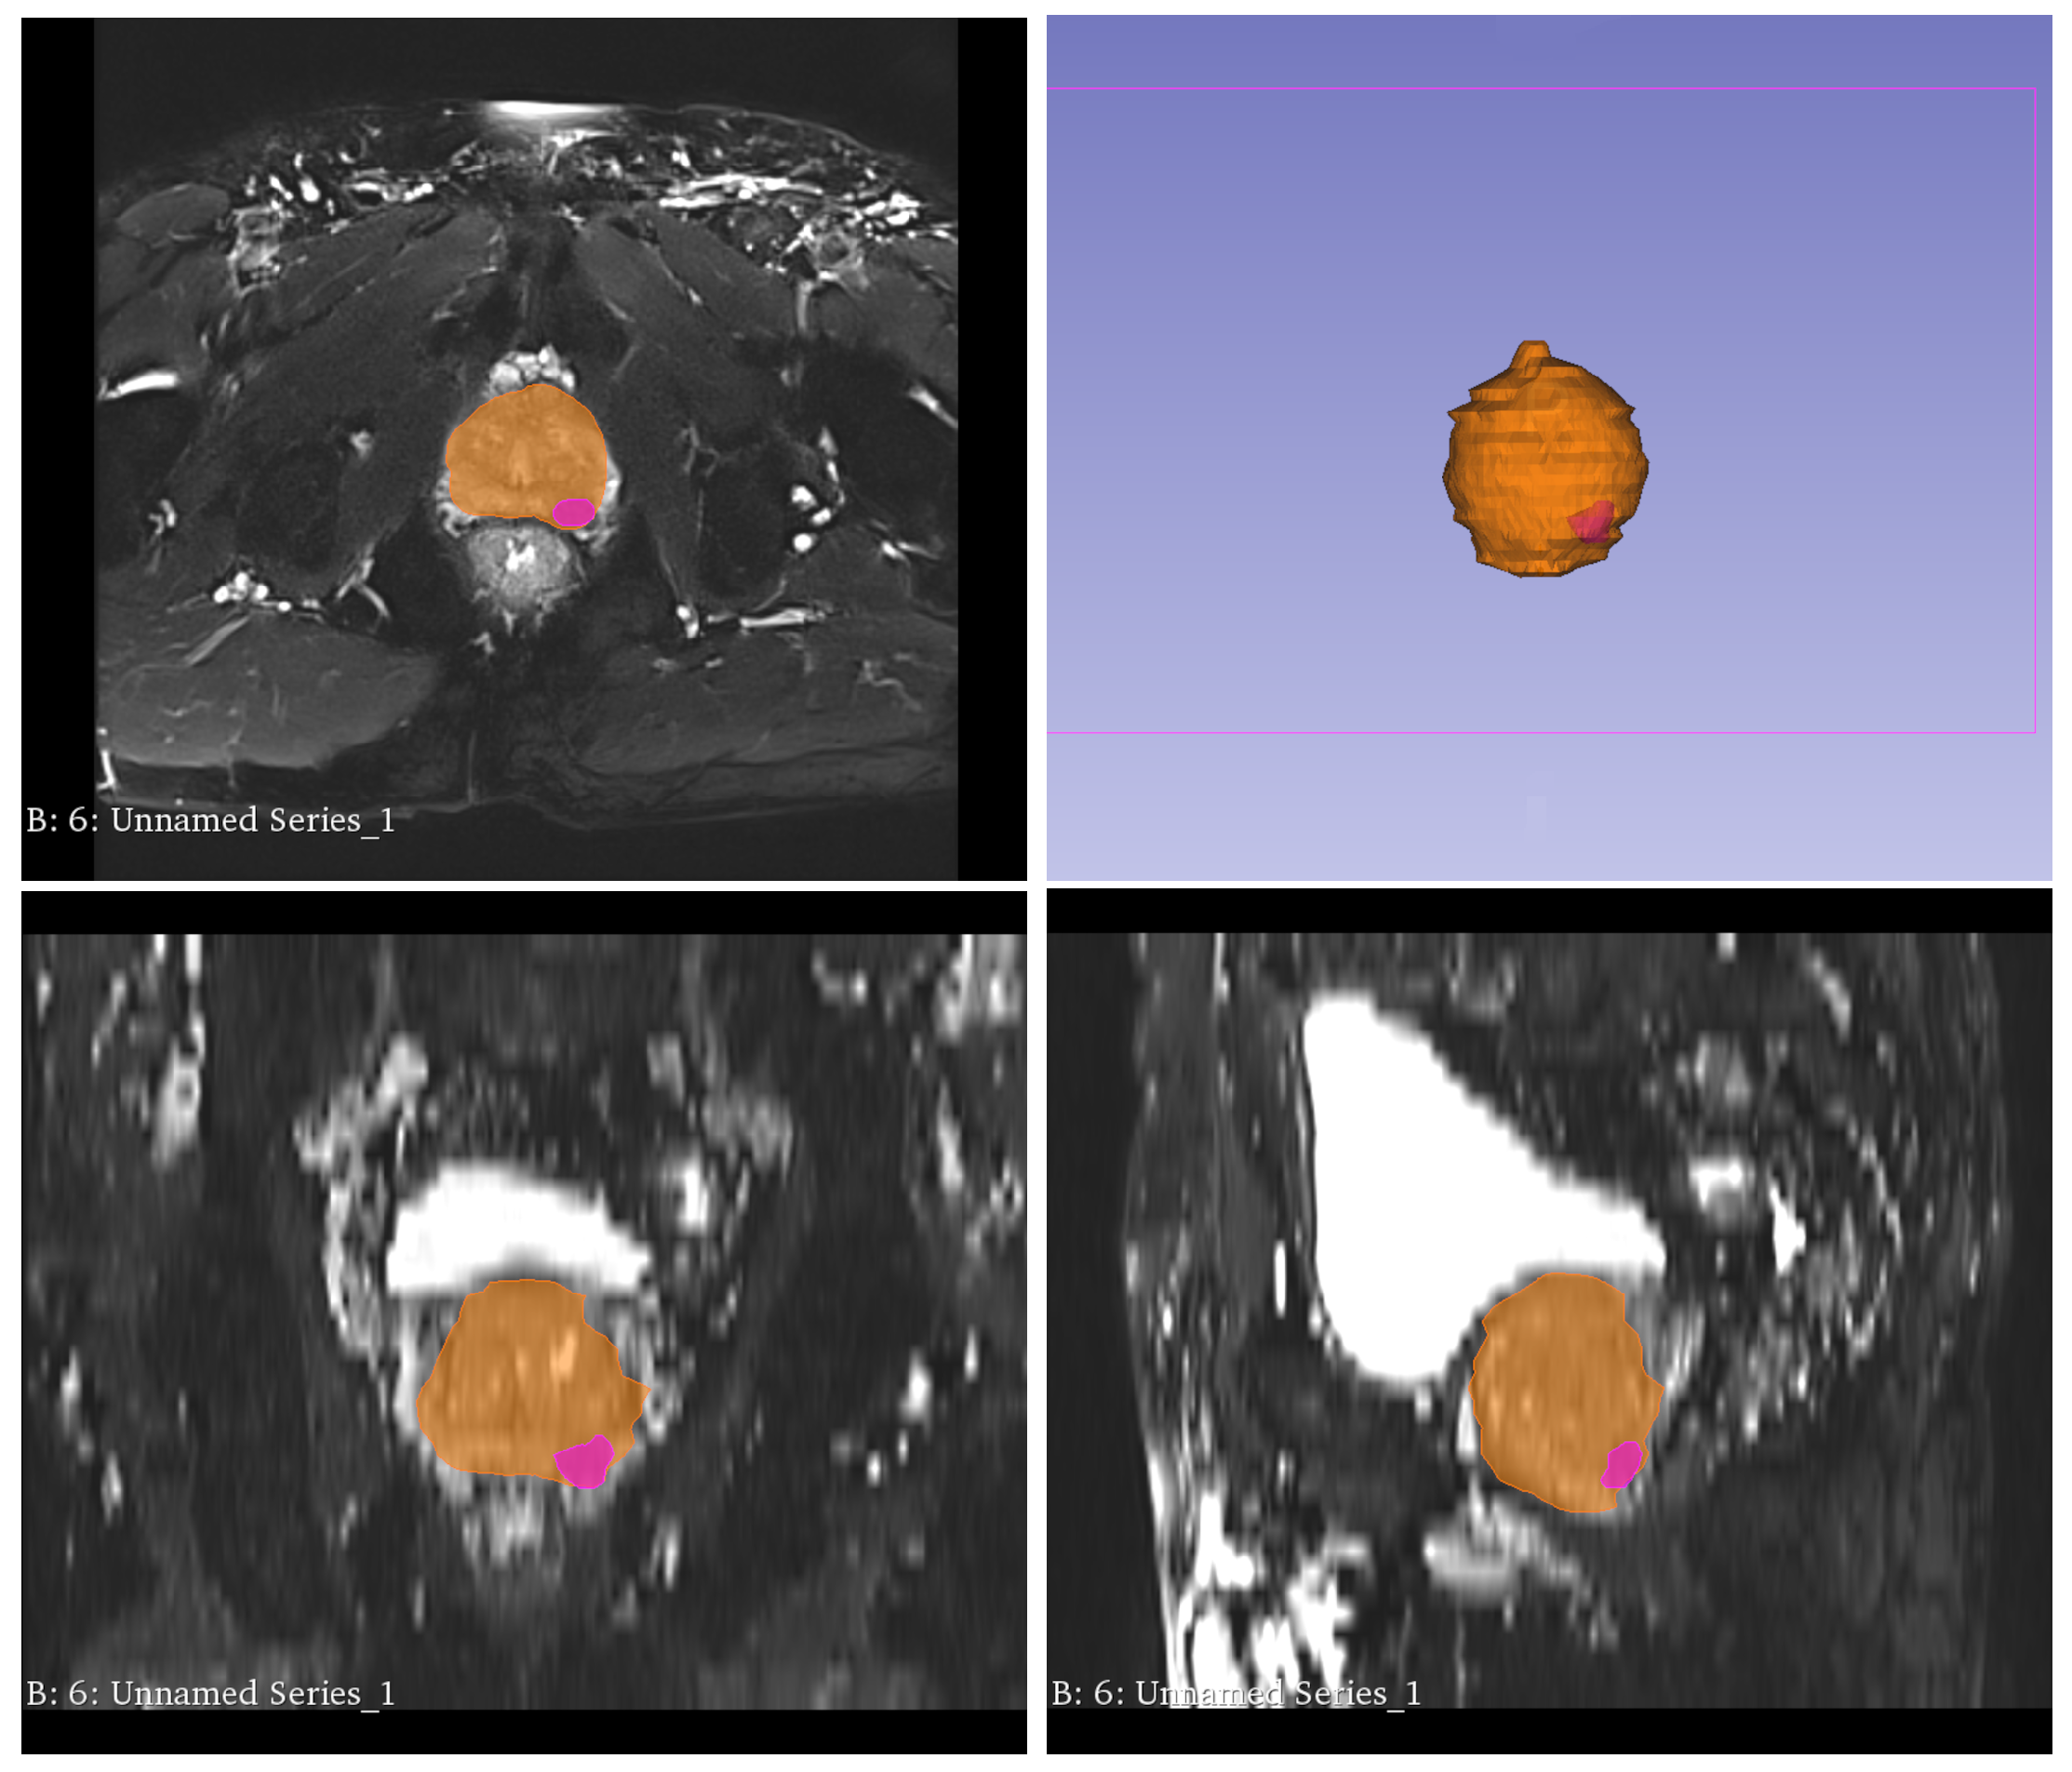

That result may significantly impact the dialogue on the adoption of deep learning-based methods and applications in healthcare and may remove one of the barriers defined as operational costs. Deploying and maintaining deep learning models requires a specific infrastructure, which impacts costs. The number of models increases cost linearly. Having a model that performs an efficient analysis on two modalities without losing the accuracy removes that constraint. Furthermore, the model learns on CT images and can effectively identify the prostate in MRI, which is a less invasive medical examination. Successful models trained on multimodal medical images reduce the need for CT scans and the risk of radiation-induced prostate cancer. The next step of the research is to detect primary prostate tumors located within the prostate organ, which is shown in Figure 12. That milestone will significantly support raiologists and medical experts in making decisions, as detecting primary prostae tumors is a long-term and difficult task. The barriers to this step are the kinds of data and detailed labels on diverse and numerous slices.

Figure 12.

Primary prostate tumors (pink color) within segmented prostate organ (orange color).